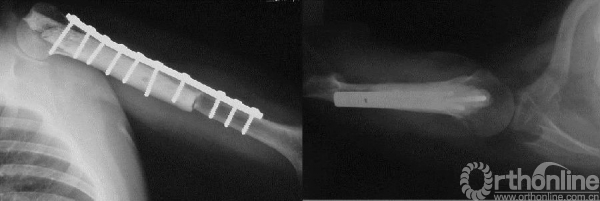

手术行病灶刮除、异体骨及人工骨植骨、钢板内固定术。

图13-6 病例二术后X线平片正侧位

术后病理示骨囊肿。